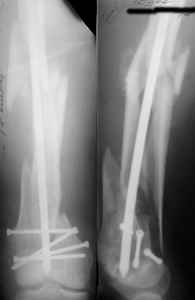

Attached are few examples from our Hospital:

Malpositioning is much too common (recurvatum, varus - valgus).

B. Fixation loosening: distal cutting of the nail, non-unions do happen (cases attached).

Locking Plating has more distal screws than any nail, fixed angles and provides much better fixation, especially in osteoporotic bone.